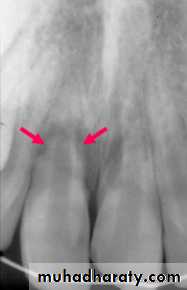

Replacement Resorption(Ankylosis)

Direct union of bone and root

Resorption of root

Replacement with bone

Direct result of loss of vital PDL